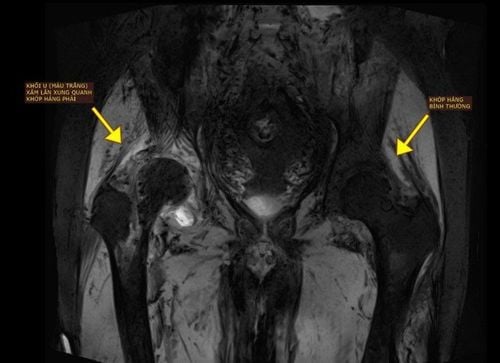

Vietnamese doctors and engineers designed artificial bones to perform surgery and saved a bone cancer patient with two extremely rare locations

For the first time in the world, Vinmec has successfully performed a simultaneous replacement of both the pelvis and a part of the femur in a single surgery to treat an extremely rare type of bone cancer